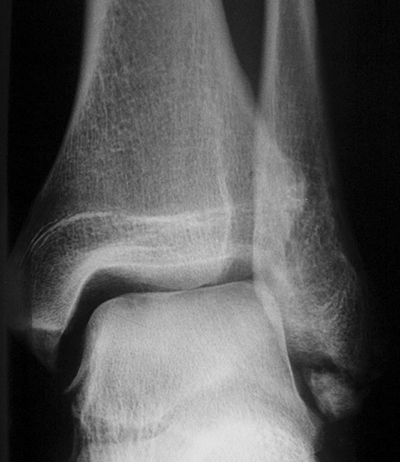

Fugengelenkfrakturen treten typischerweise vor dem 10. Lebensjahr auf, in einer Phase, in welcher die Wachstumsfugen noch weit offen sind. Dieser Frakturtyp betrifft fast ausschließlich den medialen Malleolus. Laterale Frakturen sind extrem selten, teilweise kommt es zu lateralen Bandverletzungen oder Fugenschaftfrakturen der distalen Fibula. Die Frakturlinie verläuft in einer Verlängerungslinie von der medialen Taluskante nach proximal. Häufig stellen sich Verletzungen des Innenknöchels im Röntgenbild schlechter dar, insbesondere wenn die Aufnahmen verdreht sind oder die Ebene der Fraktur bei geringer Dislokation verkippt zur Röntgenebene liegt. Besteht klinisch der geringste Hinweis auf eine Verletzung des Innenknöchels, muss aufgrund der Tragweite der Verletzung durch entsprechende Aufnahmen gegebenenfalls auch Schnittbildverfahren die Verletzung sicher diagnostiziert oder ausgeschlossen werden (Abb. 15).

„Kadiläsion“- Mediale Malleolarfraktur

Bei kindlichen Verletzungen des medialen Malleolus handelt es sich nach L. v. Laer um eine sogenannte Kadiläsion, d.h. eine Verletzung mit hohem Risiko eines schlechten Behandlungsergebnisses bei nicht korrekter Behandlung. Selbst bei optimaler Therapie ist das Risiko für spätere Wachstumsstörungen hoch, sodass diese Verletzungen nicht selten ein juristisches Nachspiel haben. Durch die Verletzung der wachstumsaktiven Zone kann es zu einem vorzeitigen Verschluss der Wachstumsfuge kommen, mit entsprechendem Fehlwachstum. Das Risiko eines vorzeitigen Verschlusses der Wachstumsfuge korreliert mit dem Ausmaß der Schädigung der wachstumsaktiven Zone. Ab dem 13. Lebensjahr wird das Risiko bei reduzierter Wachstumsaktivität zunehmend geringer.

Fugengelenkfrakturen können die Wachstumsfuge durchkreuzen (Abbildung 16a), ohne oder nur mit minimaler Beteiligung der Fuge sehr weit medial liegen (Abbildung 16b) oder durch die Fuge auslaufen (Abbildung 16c). Relevant für die Wachstumsprognose ist weniger die Form der Fraktur, sondern das Alter des Patienten zum Zeitpunkt des Traumas sowie das Ausmaß der Schädigung der Wachstumsfuge, wobei eine Korrelation mit dem Ausmaß der Dislokation besteht.